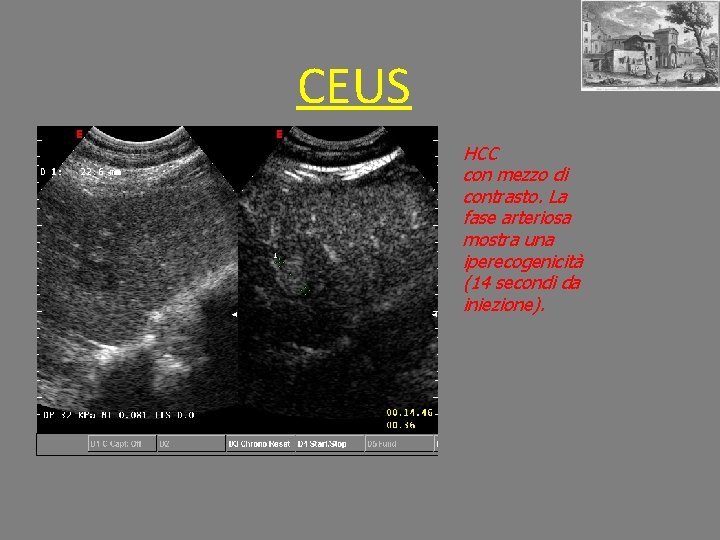

CEUS HCC con mezzo di contrasto. La fase arteriosa mostra una iperecogenicità (14 secondi da iniezione).